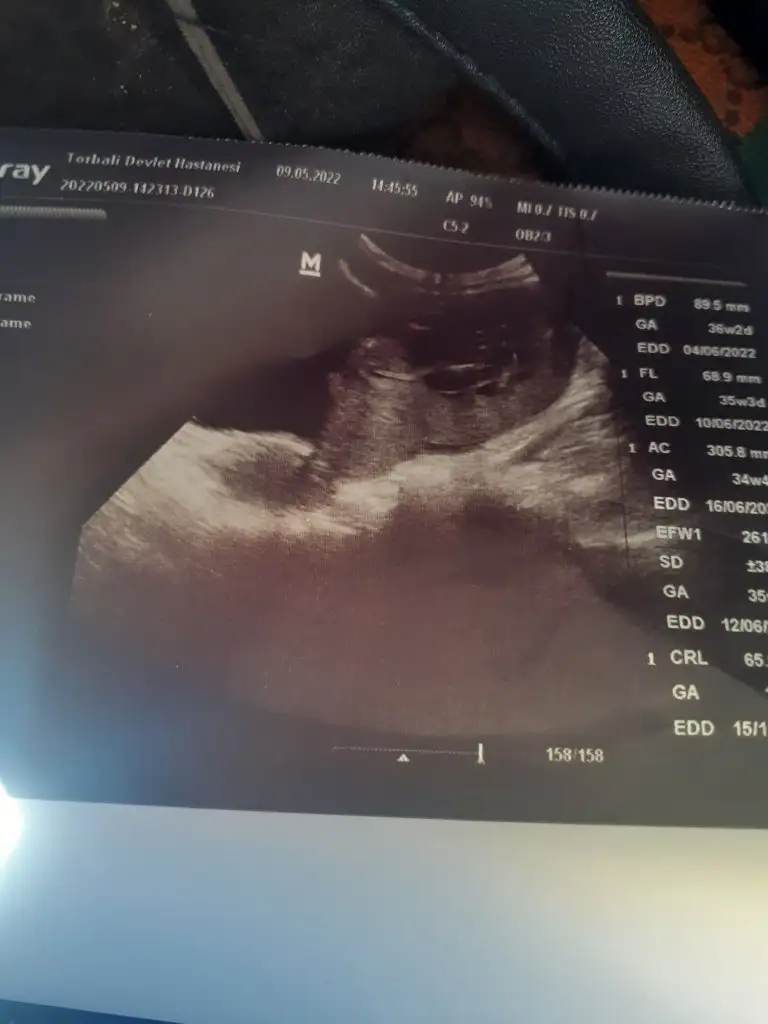

Bakarmisin

• 20220509_153718.webp

20220509_153718.webp

21,1 KB · Görüntüleme: 44

• 20220509_153714.webp

20220509_153714.webp

21,5 KB · Görüntüleme: 39

• 20220509_153706.webp

20220509_153706.webp

23,3 KB · Görüntüleme: 38

• 20220509_153651.webp

20220509_153651.webp

22,5 KB · Görüntüleme: 43